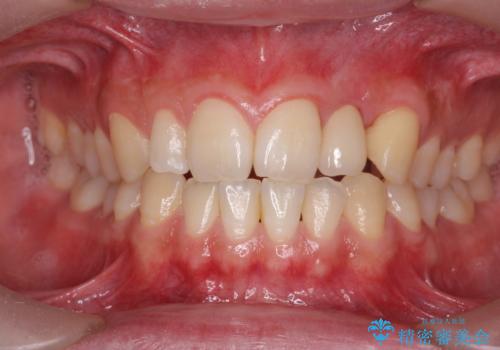

前歯部 インプラント治療

- 前歯の永久歯が元々なく、乳歯を失ったタイミングで前歯の審美性の回復を求めて来院されました。

機能・審美性の回復手段として、インプラント治療・ブリッジ・部分床義歯が考えられます。

それぞれの治療に特徴がありますが、取り外しの必要がなく隣の歯を削る必要も必要ないインプラント治療を選択されました。

- 55万円(ストローマンインプラント・ジルコニアカスタムアバットメント・骨造成・仮歯・ジルコニアクラウン)費用は治療当時の料金となります

前歯部にインプラントを埋入し、きれいに仕上げるためには骨の造成技術や歯肉の厚みを増すような処置を行い、インプラント周囲の環境を整備することが肝要です。